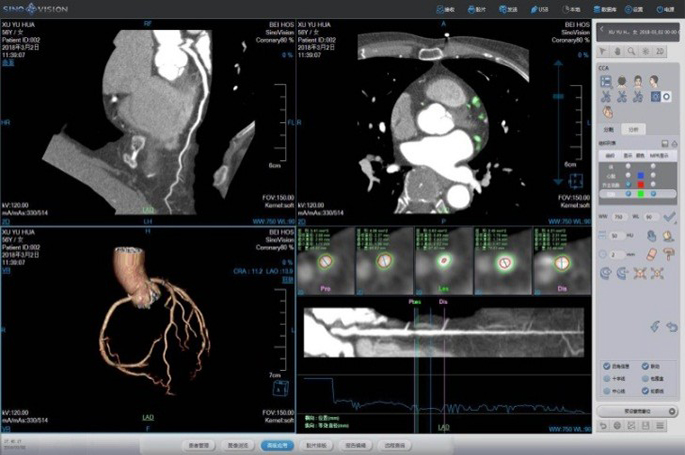

One Station Cardiac Diagnosis Analysis

Prospective ECG-triggered Mode Advanced Diagnosis-guided solution –ECG guided Cardiac Examination

• Prospective gating –Decrease dose by 30%

• ClearView –Decrease dose by 50% for every heartbeat

• Scan protocols

120 kV, 250mA (BMI ≥25)

100 kV , 200mA (BMI <25)

CearView + Prospective-triggering – low dose <3mSv